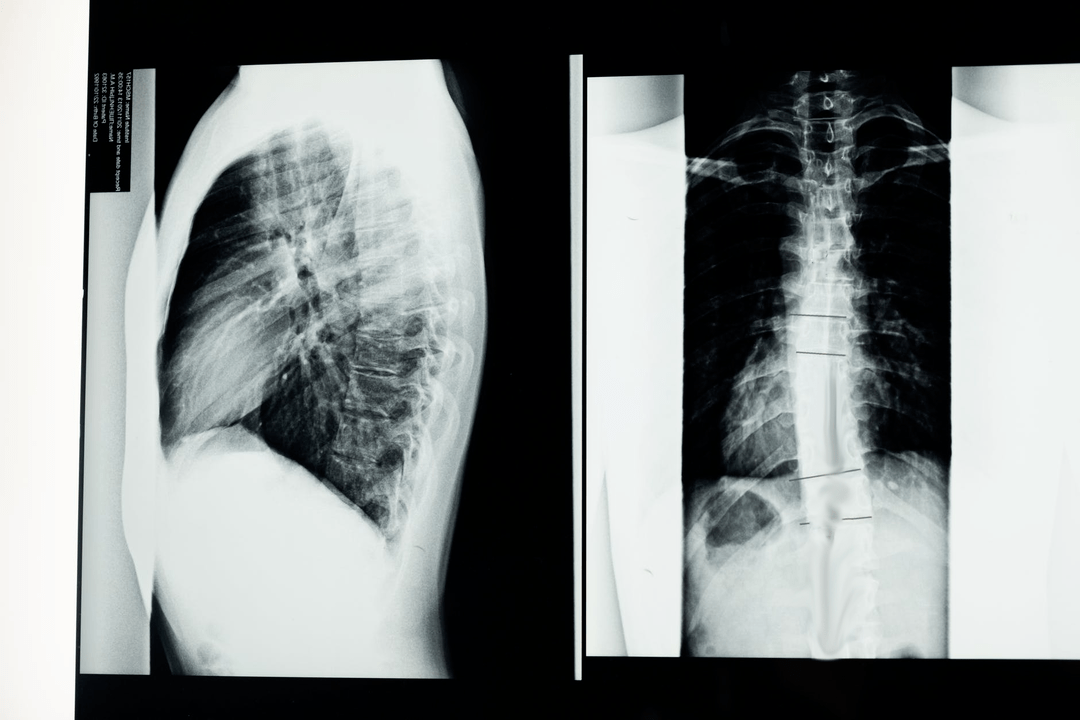

Before starting diagnostic studies, the neurologist takes the patient's medical history and carefully examines his complaints.Osteochondrosis has symptoms common to some other diseases, so it is important to be able to distinguish pathologies.X-ray studies help confirm the diagnosis of osteochondrosis: radiography, myelography and computed tomography.

A survey x-ray allows you to take an x-ray of the spine or a section of it.This allows the doctor to determine the location affected by the disease.To clarify, we will explain how osteochondrosis can be determined using an X-ray: the picture shows a narrowing of the intervertebral disc, the presence of bone growths (osteophytes) or a change in the shape of the spinal segment.